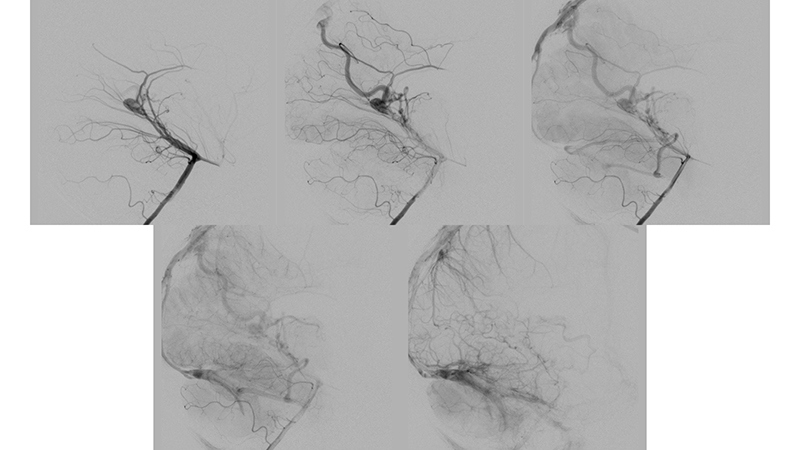

- Πλαγία λήψη κατά την έγχυση στην δεξιά έσω καρωτίδα. Υπάρχει εξεσημασμένη φλεβική συμφόρηση του άνω οβελιαίου κόλπου, προς το σύστημα της φλέβας του Troland (μπλέ βέλος), τον σηραγγώδη κόλπο και τό έδαφος του προσθίου κρανιακού βόθρου (μαύρα βέλη) και το πτερυγοειδές πλέγμα.

- Πλαγία λήψη κατά την έγχυση στην αριστερή έσω καρωτίδα. Η φλεβική παροχέτευση της αρτηριοφλεβώδους επικοινωνίας προς το σύστημα του άνω οβελιαίου κόλπου (κόκκινα βέλη) με εξεσημασμένη φλεβική συμφόρηση και κινητοποίηση παράπλευρων διαμυελικών φλεβών προς το σύστημα της επιπολής μέσης εγκεφαλικής φλεβός (μπλέ βέλος) και διά του σφηνοβρεγματικού κόλπου προς τον σηραγγώδη κόλπο ενώ το εν τω βάθει φλεβικό δίκτυο αποχετεύεται μέσω των αναστομώσεων με το σύστημα της εν τω βάθει μέσης εγκεφαλικής φλεβός (διακεκομμένο μπλέ βέλος) προς το σύστημα επίσης του σηραγγώδους κόλπου.

- Πλαγία λήψη κατά την έγχυση στην αριστερή σπονδυλική αρτηρία. Τροφοφόροι θαλαμοδιατιτραίνοντες (διακεκομμένο μαύρο βέλος) και υποεπενδυματικοί κλάδοι (διακεκομμένο μπλέ βέλος), εκ της οπισθίας αναστομωτικής και του Ρ1 τμήματος των οπισθίων εγκεφαλικών αρτηριών, που πορευόμενοι στο πλάγιο τοίχωμα της 3ης κοιλίας εκατέρωθεν, συναντούν την χοριοειδή σχισμή και εκείθεν αρδεύουν την αρτηριοφλεβώδη επικοινωνία (μαύρα βέλη). Παρατηρείται αναστροφή της ροής στον άνω οβελιαίο κόλπο με φλοιώδη παλινδρόμηση προς τα εγκεφαλικά ημισφαίρια αμφοτερόπλευρα (κόκκινα βέλη). Οι εγκάρσιοι κόλποι αποφράσσονται, και μέσω των περιμεσεγκεφαλικών φλεβών παρατηρείται παροχέτευση προς το περιμυελικό φλεβικό δίκτυο του νωτιαίου μυελού (μπλέ βέλη) το οποίο παρουσιάζει εκσεσημασμένη συμφόρηση αλλά και διά του άνω λιθοειδούς κόλπου προς τον σηραγγώδη κόλπο (μαύρα βέλη).

- Αξονική τομογραφία με σκιαγραφικό και αγγειογραφία του σπονδυλοβασικού συστήματος σε πλάγια λήψη. Διακρίνεται κατιούσα φλεβική παροχέτευση προς το περιμυελικό φλεβικό δίκτυο του νωτιαίου μυελού (μπλέ βέλη) το οποίο παρουσιάζει εκσεσημασμένη συμφόρηση.

- Καθετηριασμός και εμβολισμός με κυανοακρυλική κόλλα θαλαμοδιατιτραινόντων κλάδων.

- Καθετηριασμός και εμβολισμός με κυανοακρυλική κόλλα υποεπενδυματικών κλάδων.

- Καθετηριασμός και εμβολισμός με κυανοακρυλική κόλλα οπισθιοπλαγίων χοριοειδών κλάδων.

Το παιδί μετά τον πρώτο εμβολισμό παρουσίασε άμεση κλινική βελτίωση, με πλήρη αποκατάσταση της κινητικότητος του. - Προσθιοπίσθια λήψη κατά την έγχυση στην αριστερή έσω καρωτίδα ένα μήνα μετά την επέμβαση. Παρατηρείται θρόμβωση του ευθέως κόλπου και της περιοχής του Ληνού του Ηροφίλου καθώς και του τελικού τμήματος του άνω οβελιαίου κόλπου και των εγκαρσίων κόλπων. Ο μηχανισμός της θρομβώσεως, αποδίδεται στην σημαντική ελάττωση της ροής μέσα στο φλεβικό αποχετευτικό δίκτυο της φλέβας του Γαληνού και του ευθέως κόλπου που πιθανότατα οδήγησε σε φλεβική στάση και θρόμβωση.

- Πλαγία λήψη κατά την έγχυση στην αριστερή έσω καρωτίδα ένα μήνα μετά την επέμβαση. Παρατηρείται ελάχιστη άρδευση της επικοινωνίας από οπίσθιους χοριοειδείς κλάδους των οπισθίων εγκεφαλικών, καθώς και από θαλαμοδιατιτραίνοντες κλάδους που εκφύεται από το Ρ1 της αριστερής οπισθίας εγκεφαλικής αρτηρίας. Η φλεβική παροχέτευση της επικοινωνίας γίνεται προς την φλέβα του Γαληνού που είναι σημαντικά λιγότερο διατεταμένη, και δια μέσου επιπολής φλεβός της έσω επιφανείας του αριστερού βρεγματικού φλοιού προς τον αποσυμφορημένο πιά άνω οβελιαίο κόλπο. Η φλεβική αποχέτευση του ημισφαιρίου γίνεται προς το σύστημα του αριστερού σηραγγώδους κόλπου, με σημαντική αιμοδυναμική αποσυμφόρηση των ημισφαιρικών φλεβών που πλέον σκιαγραφούνται σε φυσιολογικό χρόνο.

- Προσθιοπίσθια λήψη κατά την έγχυση στην αριστερή σπονδυλική αρτηρία. Επανελέγχεται ελάχιστη υπολειμματική άρδευση της επικοινωνίας από οπίσθιους χοριοειδείς κλάδους των οπισθίων εγκεφαλικών, καθώς και από θαλαμοδιατιτραίνοντες κλάδους που εκφύεται από το Ρ1 της αριστερής οπισθίας εγκεφαλικής αρτηρίας, με θρόμβωση του ευθέως κόλπου και της περιοχής του Ληνού του Ηροφίλου καθώς και του τελικού τμήματος του άνω οβελιαίου κόλπου και των εγκαρσίων κόλπων.

- Πλαγία λήψη κατά την έγχυση στην αριστερή σπονδυλική αρτηρία. Η φλεβική παροχέτευση γίνεται προς την φλέβα του Γαληνού, και διά μέσου επιπολής φλεβός προς την έσω επιφάνεια του αριστερού βρεγματικού λοβού προς τον άνω οβελιαίο κόλπο, κατά την μετάπτωση του μέσου προς οπίσθιο τριτημόριο. Επίσης μέσω υποεπενδυματικών φλεβών που πορεύονται ενδοκοιλιακά αμφοτερόπλευρα και εκβάλλουν διά των άνω λιθοειδικών φλεβών προς το τους εγκαρσίους κόλπους, με πορεία προς τοην περιοχή του Ληνού που φαίνεται να έχει επανασηραγγοποιηθεί. Παρατηρείται αποσυμφόρηση του περιμεσεγκεφαλικού φλεβικού δικτύου με σημαντική ελάττωση της φλεβικής συμφορήσεως περιμεσεγκεφαλικά καθώς και προς τον νωτιαίο μυελό.

Ως αποτέλεσμα της ανωτέρω αιμοδυναμικής μεταβολής και με δεδομένη την ιακνοποιητική κλινική βελτίωση, αποφασίσθηκε να μην γίνει επέμβαση και ο ασθενής να τεθεί υπό χαμηλού μοριακού βάρους ηπαρίνη λόγω της θρομβώσεως των οπισθίων φλεβωδών κόλπων. - Δύο χρόνια αργότερα, υπερεκλεκτικός καθετηριασμός υποεπενδυματικών και χοριοειδών τροφοφόρων κλάδων από το Ρ1, Ρ2 και Ρ3 των οπισθίων εγκεφαλικών αρτηριών.

- Υπερεκλεκτικός καθετηριασμός υποεπενδυματικών και χοριοειδών τροφοφόρων κλάδων από το Ρ1, Ρ2 και Ρ3 των οπισθίων εγκεφαλικών αρτηριών.

- Τελική αγγειογραφία επανελέγχου του σπονδυλοβασικού μετά την δεύτερη συνεδρία εμβολισμού. Παραμένουν δύο με τρεις μικροί τροφοφόροι αρτηριακοί θαλαμοδιατιτραίνοντες κλάδοι από το Ρ1 τμήμα της αριστερής οπίσθιας εγκεφαλικής αρτηρίας, που λόγω του πολύ μικρού νεγέθους των θα αντιμετωπισθούν μετά από 2 έτη. Η φλεβική παροχέτευση γίνεται προς την φλέβα του Γαληνού, και διά μέσου επιπολής φλεβός προς την έσω επιφάνεια του αριστερού βρεγματικού λοβού προς τον άνω οβελιαίο κόλπο. Οι εγκάρσιοι κόλποι και ο Ληνός έχουν επανασηραγγοποιηθεί.

- Παρατηρείται πλήρης αποσυμφόρηση του περιμεσεγκεφαλικού φλεβικού δικτύου με σημαντική ελάττωση της φλεβικής συμφορήσεως περιμεσεγκεφαλικά καθώς και προς τον νωτιαίο μυελό.